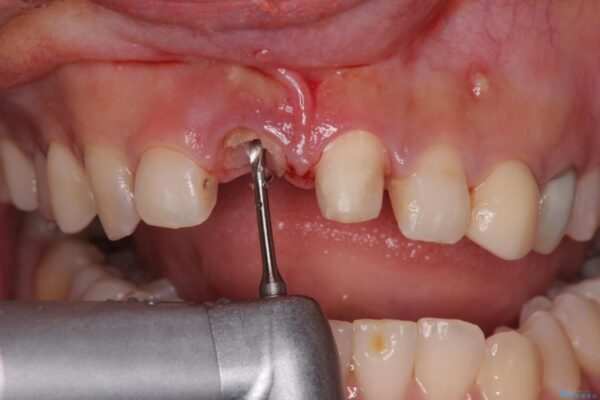

治療途中

• 「抜歯してブリッジ」と言われた20代女性が選んだ治療とは|たった4か月で自然な笑顔に抜歯即時インプラント+審美補綴の症例 治療途中画像

▶右上中切歯

抜歯後、即時インプラント埋入

審美性を考慮し、仮歯を即日装着

治療期間を最小限に抑えつつ、自然な前歯のラインと歯ぐきの形を維持